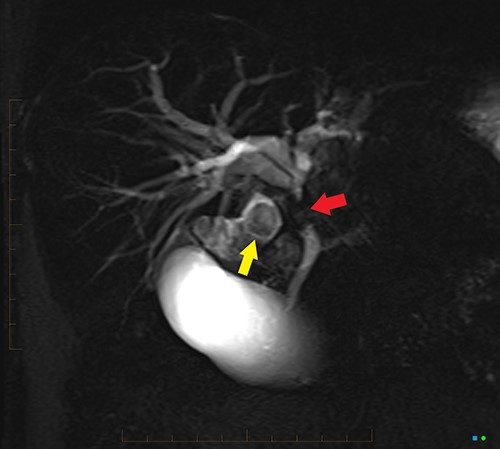

An ultrasound of the abdomen revealed a large gallstone in the gallbladder neck measuring 36 mm with mild biliary dilatation (Fig. 1). Magnetic resonance cholangiopancreatography (MRCP) revealed an irregular long stricture of the extrahepatic bile duct beginning distal to the primary biliary confluence, involving the common hepatic duct for a distance of 20 mm (Fig. 2). A multiphase liver magnetic resonance imaging was performed which confirmed a malignant appearing stricture of the common hepatic duct and showed an ill-defined soft tissue lesion in the porta hepatis between the gallbladder neck and the common hepatic duct (Fig. 3). Her Ca 19.9 was 160 kU/L (ref range < 35 kU/L).

2D projectional MRCP reveals abrupt segmental stricture (red arrow) of the common hepatic duct with marked intrahepatic biliary dilation. Gall bladder is distended and there is a calculus (yellow arrow) in the gall bladder neck.